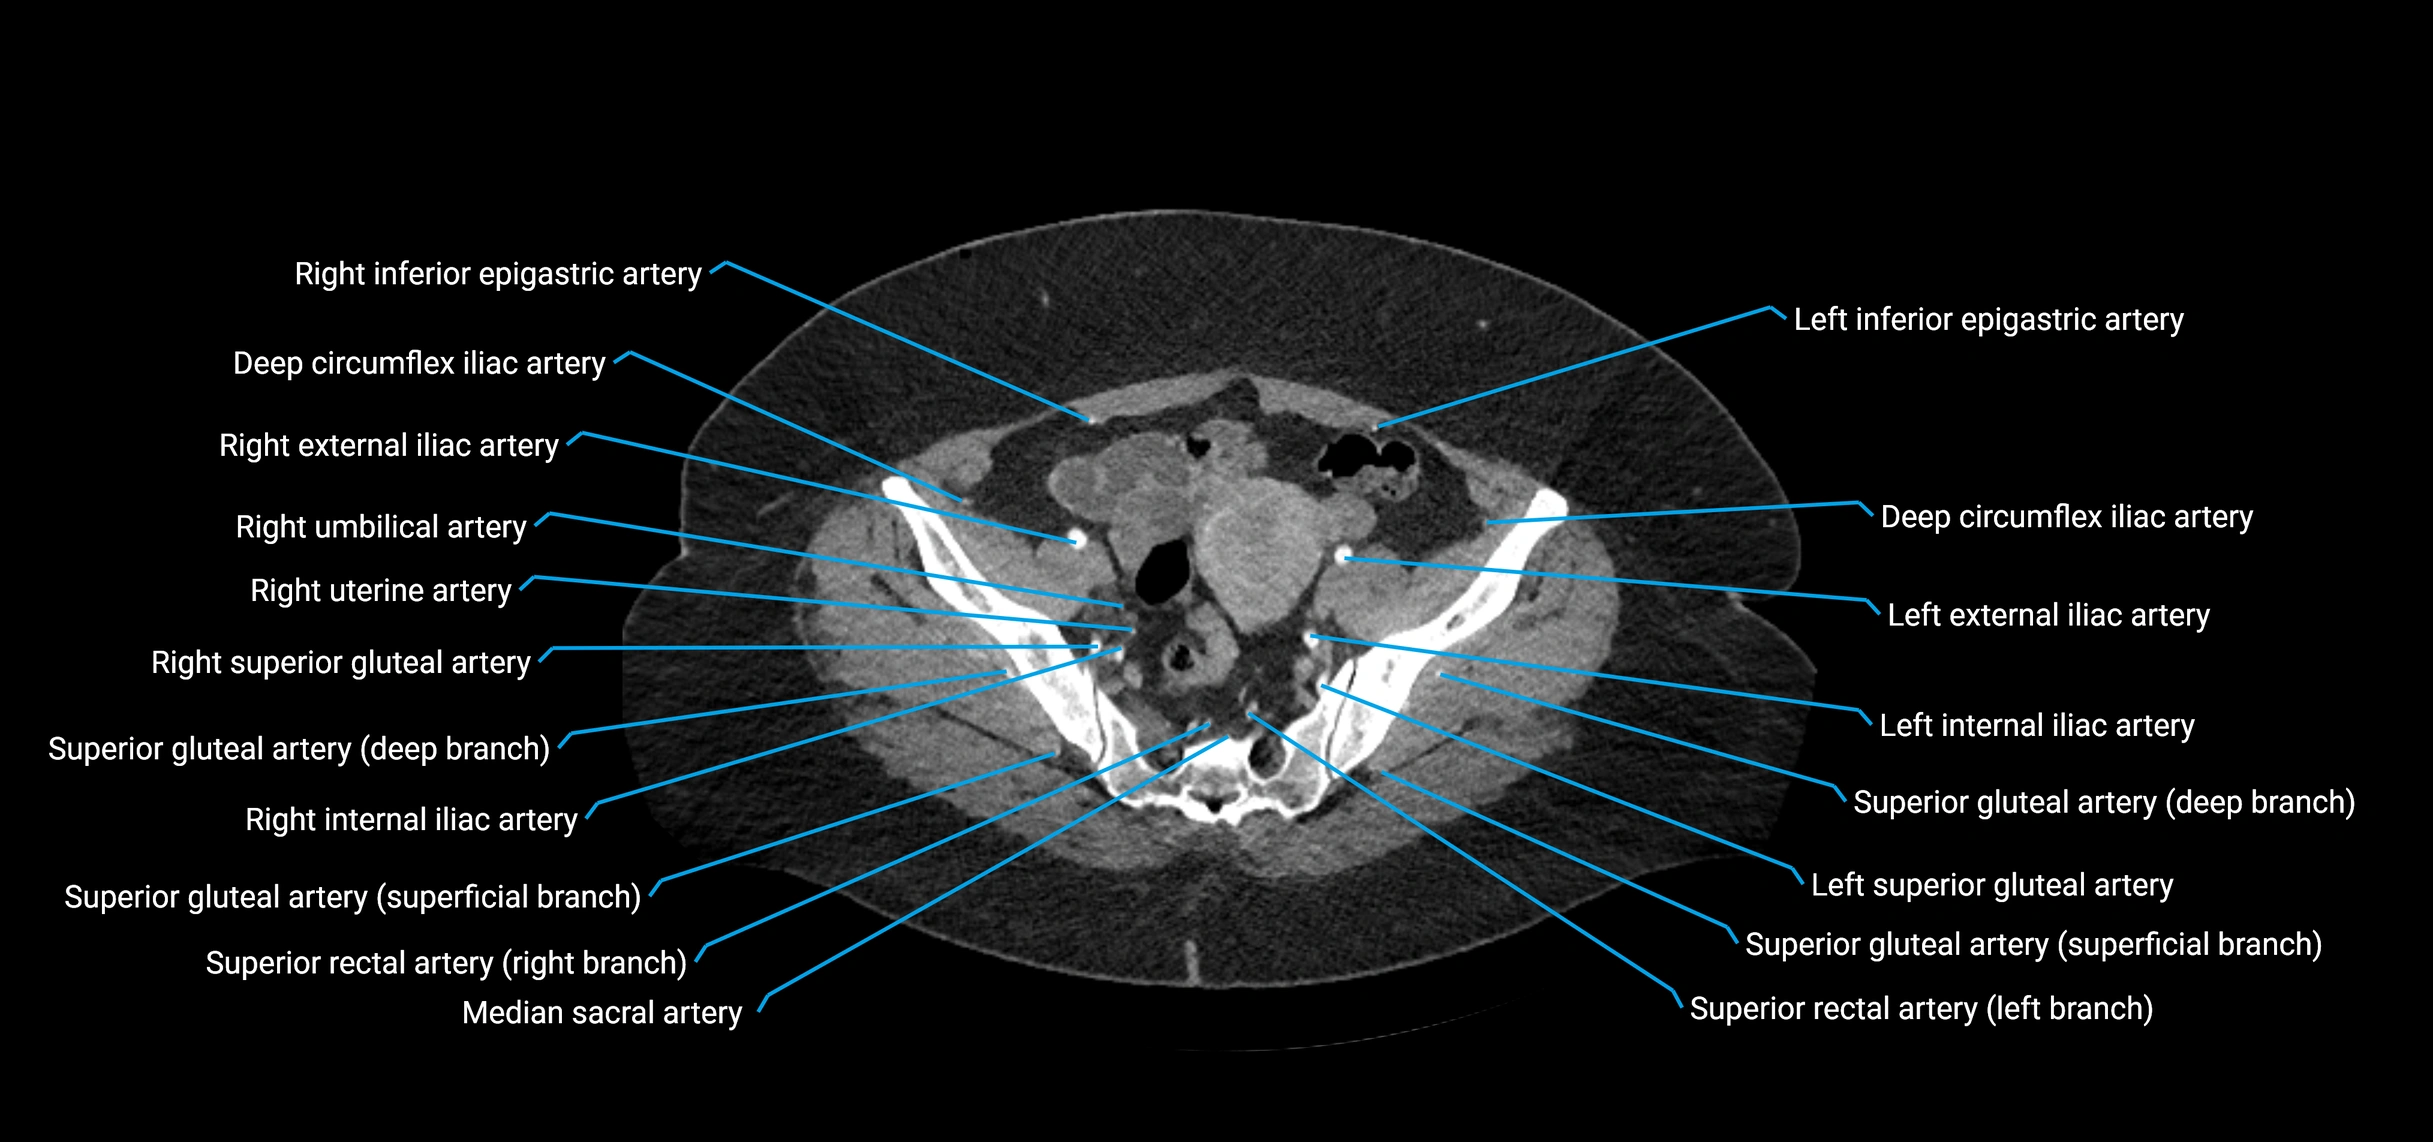

Contrast-enhanced CT (CTA):

• Gold standard for abdominal aortic imaging

• Provides excellent detail of lumen, wall, aneurysm, thrombus, and branch vessels

• Multiplanar and 3D reconstructions help in aneurysm measurement, stent graft planning, and dissection evaluation

• Detects acute rupture, traumatic injury, or occlusion with high sensitivity